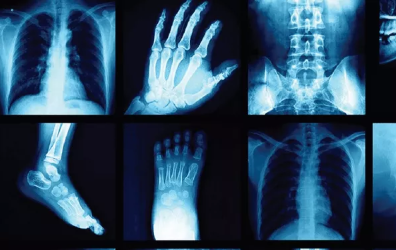

AI最直接转变的医疗保健子领域是在皮肤病学、放射学或病理学等领域中基于图像的诊断方法。在一项开创性研究中,Esteva等人利用Google Inception卷积神经网络(CNN)架构从皮肤病变图像中对非黑色素瘤和黑色素瘤皮肤癌进行分类,并获得了与专家同等的结果。在最近的一项研究中,Campanella等人展示了AI如何通过使用针头活检病理切片的数字化图像作为模型中的特征来准确地区分前列腺癌。